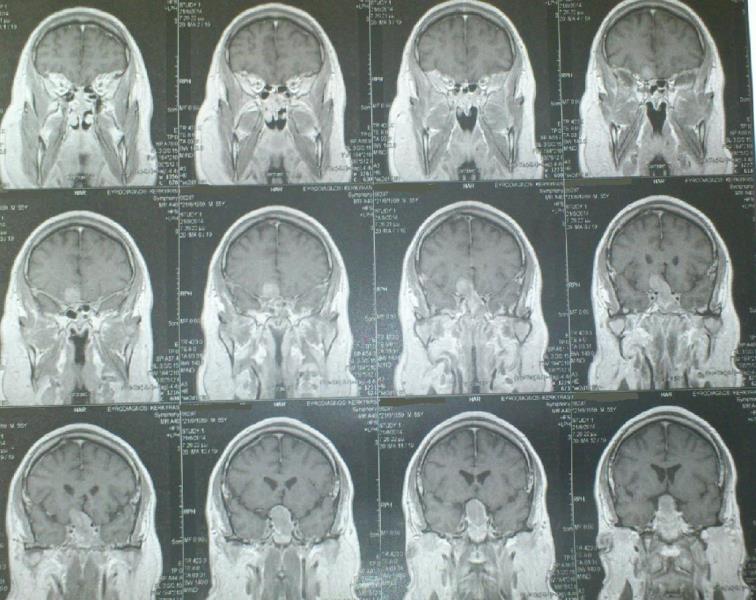

Ασθενής   55 ετών  ο οποίος είχε υποβληθεί  προ 3μήνου σε ενδοσκοπική διασφηνοειδική αφαίρεση μακροαδενώματος υπόφυσης  ( αδύνατη λόγω σκληρής σύστασης του όγκου η αφαίρεση του υπερεφιππιακού τμήματος του όγκου) προσήλθε στην κλινική μας  με σκοπό την αφαίρεση  του υπερεφιππιακού τμήματος του όγκου  δια υπερόφρυας τομής δέρματος και δεξιάς mini orbitozygomatic keyhole approach.  Η μετεγχειρητική του πορεία ήταν ομαλή με περαιτέρω βελτίωση των οπτικών του πεδίων ( αρχική μικρή  βελτίωση μετά την ενδοσκοπική διασφηνοειδική προσπέλαση ) και ο απεικονιστικός έλεγχος ανέδειξε την πλήρη αφαίρεση του υπολειμματικού όγκου.

Προεγχειρητικός απεικονιστικός έλεγχος